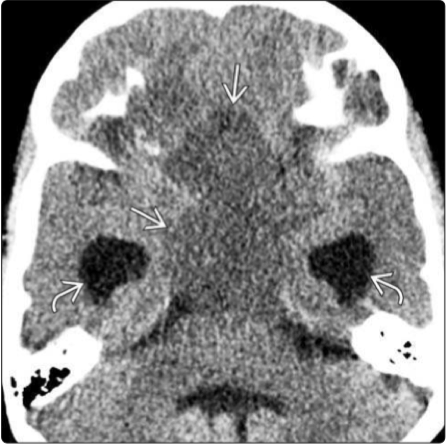

图:CT显示下丘脑-视交叉型PA,轮廓清晰、分叶形的低密度的鞍上占位,引起阻塞性脑积水。